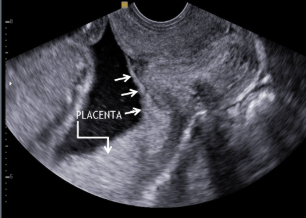

what is this image showing?

placenta previa